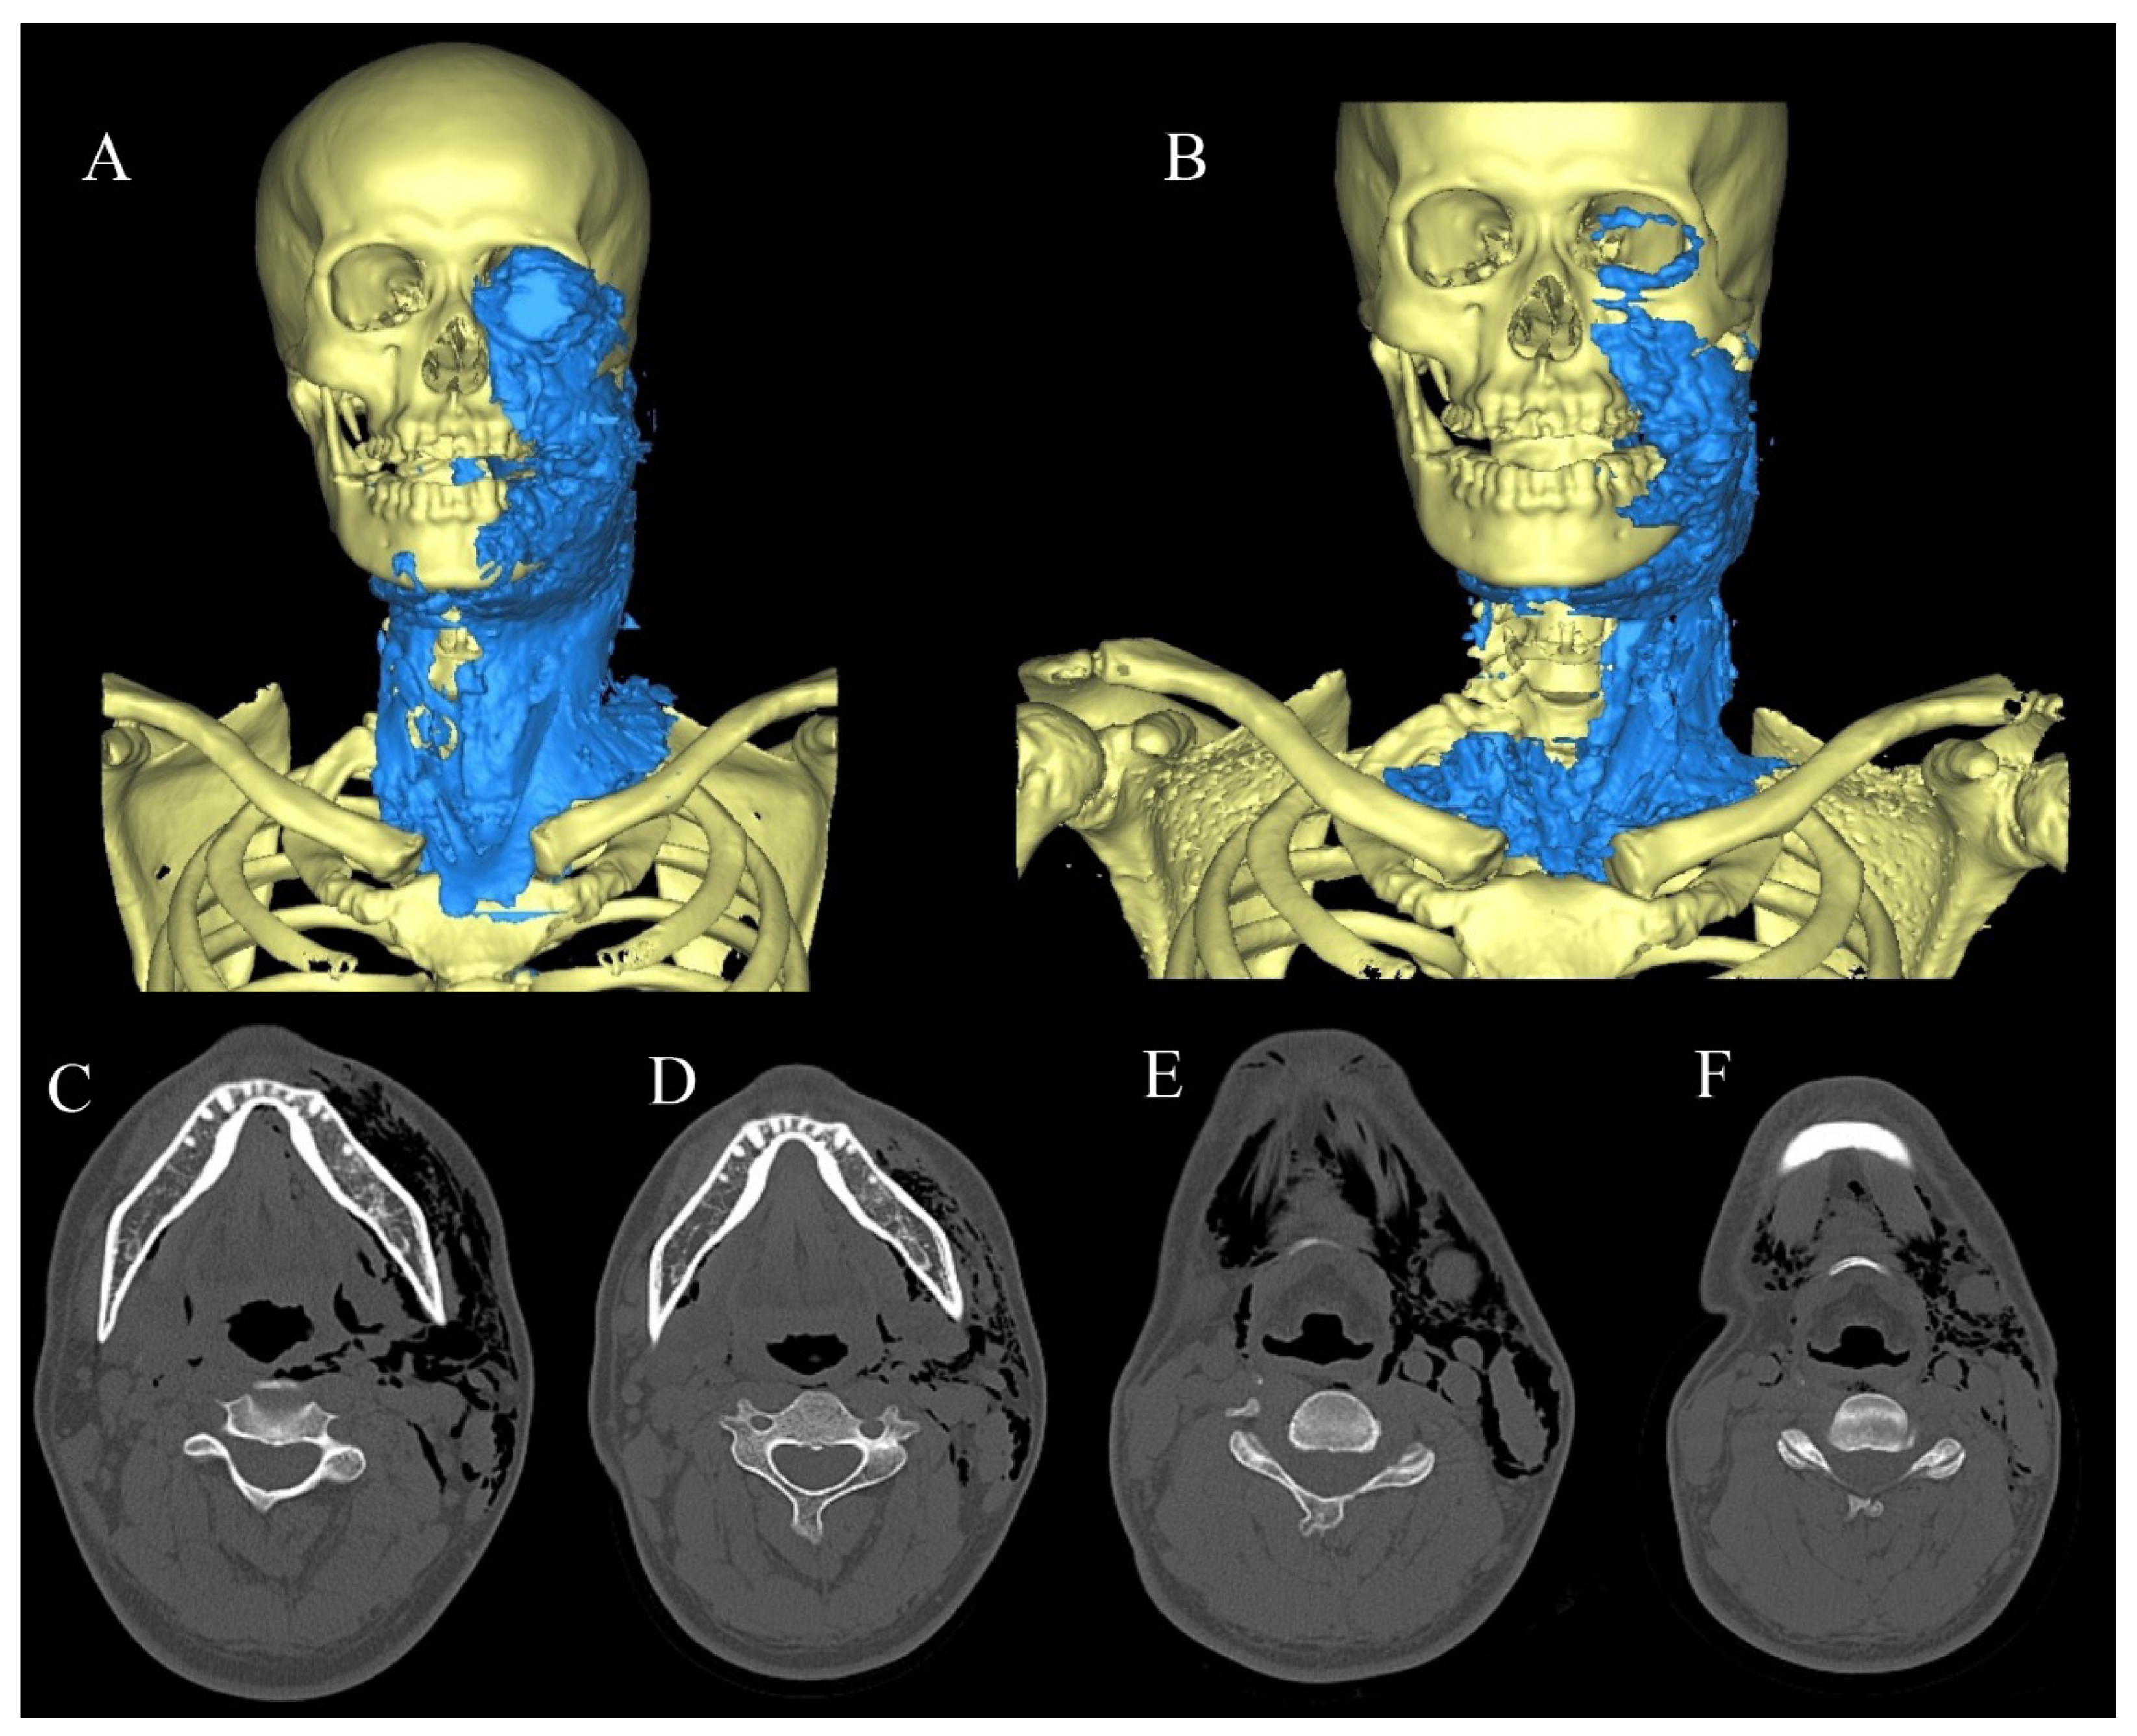

2.3.1. Case 1

2.3.2. Case 2